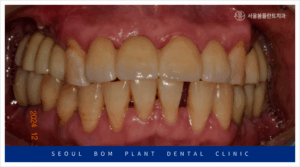

양측 위아래 어금니의

임플란트 보철물이 마무리되고 나서

앞니 심미보철치료를 진행하였는데요.

앞니는 심미성이 중요한

부위이다 보니 치아를 다듬기 전

환자분과 함께 색상과 모양을

꼼꼼하게 확인하는 작업을 거쳤으며

보철물 수복에

필요한 만큼의 양만 삭제하여

신경치료 없이 진행을 하였습니다.

앞니도 어금니와 마찬가지로

심미성이 높은 지르코니아

보철물로 수복해 드리면서

모든 치료를 마무리해 드렸는데요.

환자분께서는 임플란트를

사용하실 때보다

훨씬 더 심미적여서

마음에 드신다고 말씀해 주셨으며,

양측 어금니의 식사가 가능해져

만족해 하셨는데요.